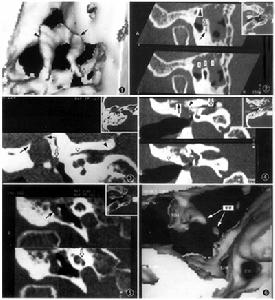

慢性化膿性中耳炎病理改變限於中、下鼓室黏膜病變侵蝕骨質,有肉芽及息肉,有膽脂瘤形成,耳流膿間歇流膿,粘液或粘膿性,不臭持續流膿,臭持續流膿,可有白色鱗片、豆渣樣物,惡臭鼓膜緊張部中央性穿孔緊張部大穿孔或邊緣性穿孔,可累及鼓環鬆弛部穿孔或邊緣性穿孔聽力傳導性聾傳導性聾或混合性聾傳導性聾或混合性聾乳突X線攝片乳突多為硬化型,骨質無缺損破壞硬化型或板障型,有骨質缺損破壞有膽脂瘤空洞形成,邊緣濃密銳利

(一)單純型:最常見,多由於反覆發作的上呼吸道感染時,致病菌經咽鼓管侵入鼓室所致,又稱咽鼓管室型。炎性病為主要位於鼓室黏膜層,鼓室黏膜充血、增厚,圓形細胞浸潤,杯狀細胞及腺體分泌活躍。臨床特點為;耳流膿,多為間歇性,呈粘液性或粘液膿性,一般不臭。量多少不等,上呼吸道感染時,膿量增多。鼓膜穿孔多為緊張部中央性,大小不一,但穿孔周圍均有殘餘鼓膜。鼓室黏膜粉紅色或蒼白,可輕度增厚。耳聾為傳導性,一般不重。乳突X線攝片常為硬化型,而無骨質缺損破壞。

(二)骨瘍型:又稱壞死型或肉芽型,多由急性壞死型中耳炎遷延而來。組織破壞較廣泛,病變深達骨質,聽小骨、鼓竇周圍組織可發生壞死;黏膜上皮破壞後,局部有肉芽組織或息肉形成。此型特點:耳流膿多為持續性,膿性間有血絲,常有臭味。鼓膜緊張部大穿孔可累及鼓環或邊緣性穿孔。鼓室內有肉芽或息肉,並可經穿孔突於外耳道。傳導性聾較重。乳突X線攝片為硬化型或板障型,伴有骨質缺損破壞。

(三)膽脂瘤型:膽脂瘤非真性腫瘤,而為一位於中耳、乳突腔內的囊性結構。囊的內壁為復層鱗狀上皮,囊內充滿脫落上皮、角化物質及膽固醇結晶,囊外側以一層厚薄不一的纖維組織與其鄰近的骨壁或組織緊密相連。由於囊內含有膽固醇結晶,故稱膽脂瘤(cholesteatoma)。

慢性化膿性中耳炎--X光片對骨瘍型慢性化膿性中耳炎的治療也應酌性處理,骨瘍型常伴有中耳腔內芽,由於它堵塞鼓膜穿孔,使膿液難以排除,若容易取出中耳肉芽則應取出,促進膿液流出,如果觸動肉芽會出現眩暈和面肌抽搐,則說明肉芽與耳內的重要機構相關連。凡遇到上述情況不得盲目牽拉肉芽組織,若乳突X線拍片顯示的乳突骨質破壞,則應進行乳突根治手術治療

對膽脂瘤型慢性化膿性中耳炎的治療,則應儘早治療,或早施行乳突根治手術。因為此型極易破壞鼓室和乳突的結構,使半規管和面神經的骨管破壞吸收,以致出現迷路炎和面神經癱瘓;同時也能破壞鼓室與乳突的頂壁,在中耳乳突和顱腦間的骨板形成缺損,乳突後部的乙狀竇骨壁也可因為膽脂瘤壓迫而吸收破壞,極易造成細菌進行顱內,引起化膿性腦膜炎,顱內膿腫等嚴重的顱內併發症。慢性中耳炎併發症多,危害也大,因中耳炎症反覆發作,內耳的細菌也會逐漸變異為去它乾菌而產生抗藥,建議最好是選擇專業性對症治療,而採用中醫藥治療慢性中耳炎,特別是對很多抗生素而產生耐藥的患者.

慢性化膿性中耳炎(二)骨瘍型:乳突X線攝片為硬化型或板障型,伴有骨質缺損破壞。

(三)膽脂瘤型:乳突X線攝片示上鼓室、鼓竇或乳突有骨質破壞區,邊緣多濃密、整齊。